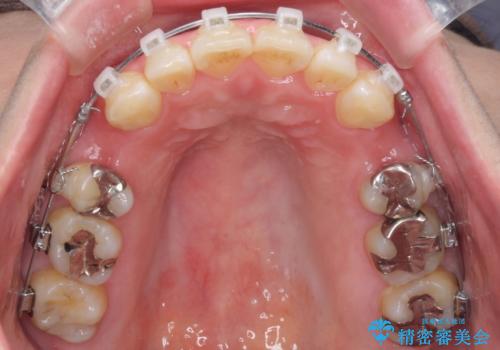

- クリアブラケット

上下左右の歯を1本ずつ、合計4本抜歯して、ワイヤーにて矯正することとなりました。

もともと下の前歯の永久歯が1本欠損しており、抜歯部位の選択を考慮しなければならない症例でした。シミュレーションを事前に行い、下顎の抜歯部位を決定しました。